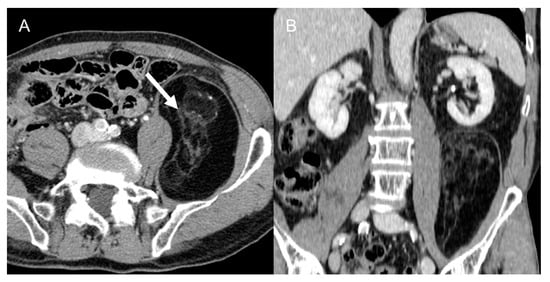

3.4. Nerve Sheath Tumors (NST)

In the retroperitoneum, a mass originating proximally to the spine, in the psoas muscle, in the sciatic nerve, or sacral plexus, or involving the neural foramina (which must be checked) can suggest a neural origin [11,47]. Schwannoma is the most frequent benign tumor (Figure 6), while MPNST is the most frequent malignant one [11]. Benign sporadic schwannomas have an unknown etiology, but if multiple lesions are seen, neurofibromatosis should always be ruled out, as it is associated with a higher risk of malignant degeneration [12,34,47].

Figure 6.

Retroperitoneal schwannoma in 66-year-old woman. Axial (A) and coronal (B) non-contrast CT images show 5.4 cm homogeneously hypodense lesions with posteriorly to the right psoas muscle (arrow).

Benign NST are usually rounded and well defined, with subtle, homogeneous enhancement, but the differential diagnosis with MPNST is oftentimes not doable on imaging [11,40]. The presence of ill-defined, infiltrative, margins, inhomogeneous peripheral enhancement, osseous involvement or encasement of nearby structures and vessels, sudden fast growth and pain are all factors pointing towards MPNST [11,12,34,35]. MPNST MRI signal is inhomogeneous, with T1 isointensity and T2 hyperintensity, cystic degeneration and lack of capsulation [40].